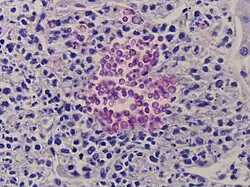

Хронический, генерализованный (гранулёматозный) кандидоз

.jpg)